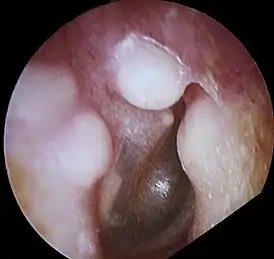

![]() Остеома наружного слухового прохода | |